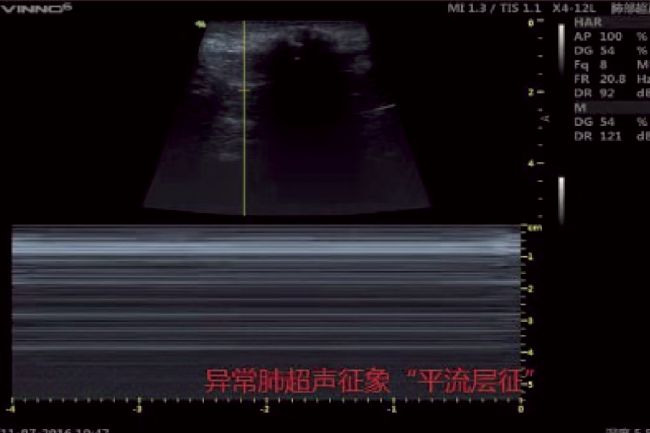

超聲波除了具有應(yīng)用于滅殺病毒的可能性,目前其在病毒的醫(yī)療診斷治療領(lǐng)域或是各種微生物實(shí)驗(yàn)研究中也有著相當(dāng)廣泛的應(yīng)用。比如當(dāng)前新冠病毒的監(jiān)測(cè)診斷領(lǐng)域中必要的超聲成像技術(shù),其可以為臨床醫(yī)生及時(shí)提供患者的各種重要生命體征,在急性重癥肺炎的診斷、治療以及療效評(píng)估上具有不可替代的地位。

肺炎患者M(jìn)型超聲圖像(平流層征)